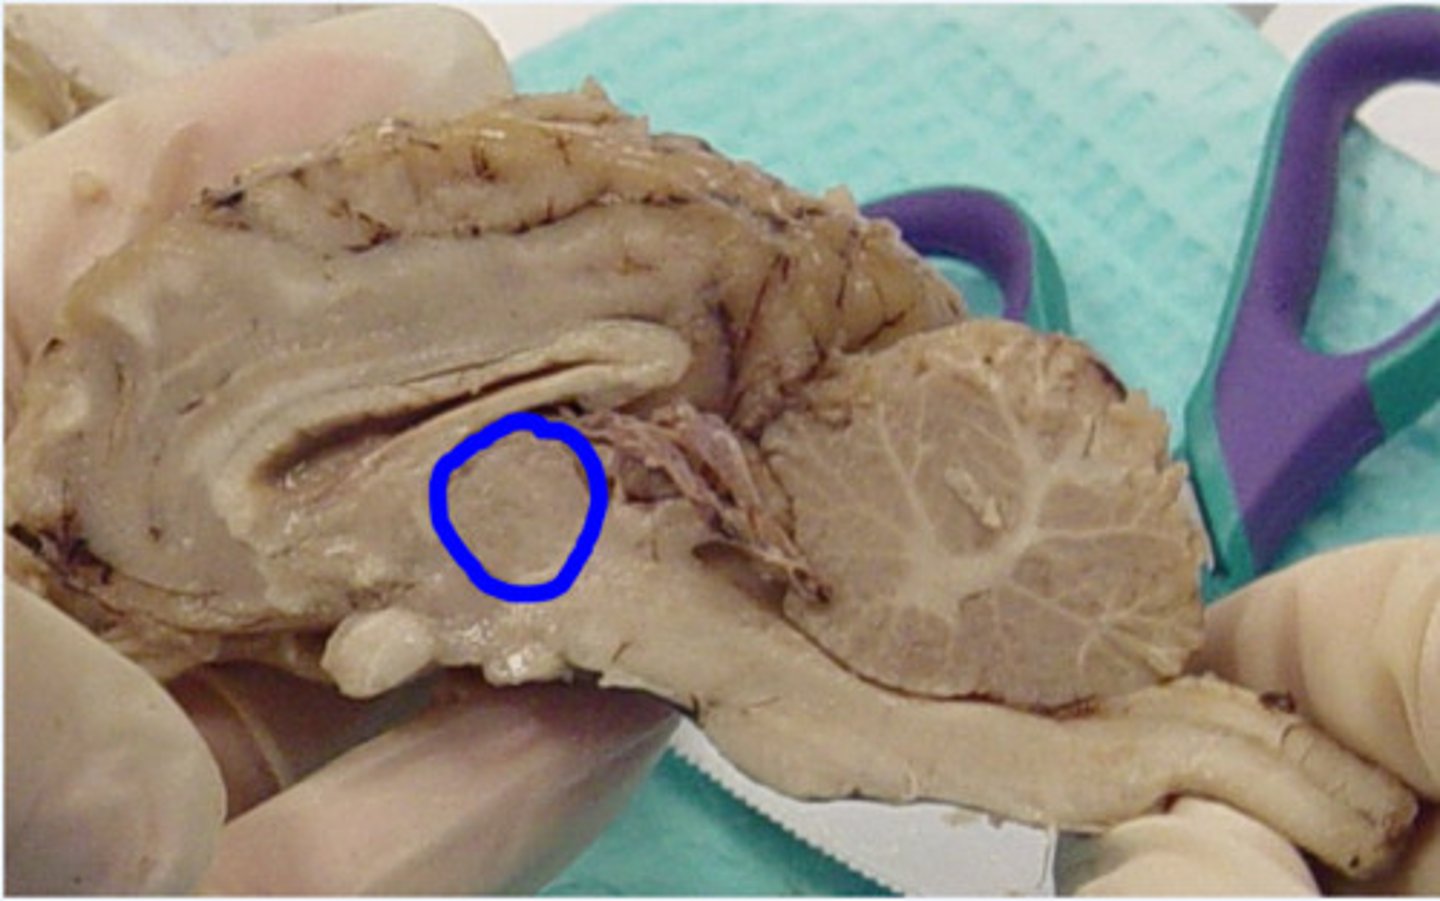

Thalamus

What is this?